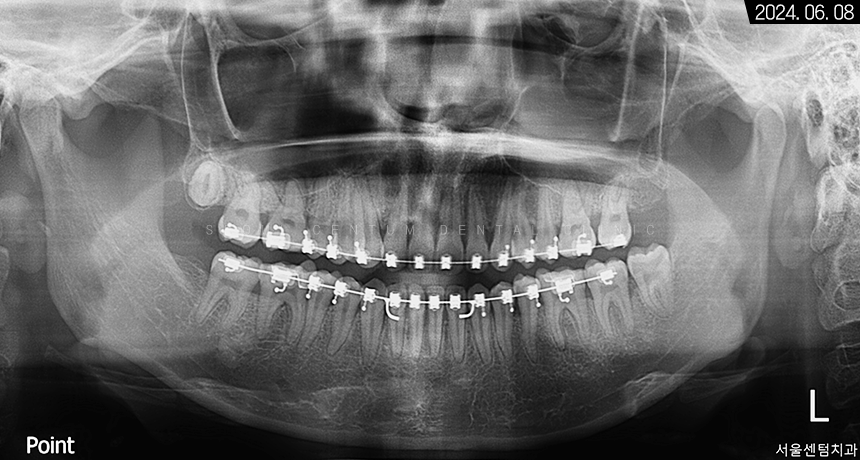

총 1년 5개월 정도의 기간이 지난 후

기존 장치를 모두 떼어내고 나서

유지 장치를 붙여드렸습니다.

파노라마 사진으로 보면

전치부에 예쁘게 붙어있는

유지 장치를 볼 수 있습니다.

또한 초반에 보였던 치간 이개가 해소되었으며

휘어졌던 하악 앞니 치근의

수직 상태가 정상을 회복하였다는 걸 알 수 있습니다.

환자분이 발치에 대한 거부감이 있으셨기에

사랑니는 고스란히 남겨드렸습니다.